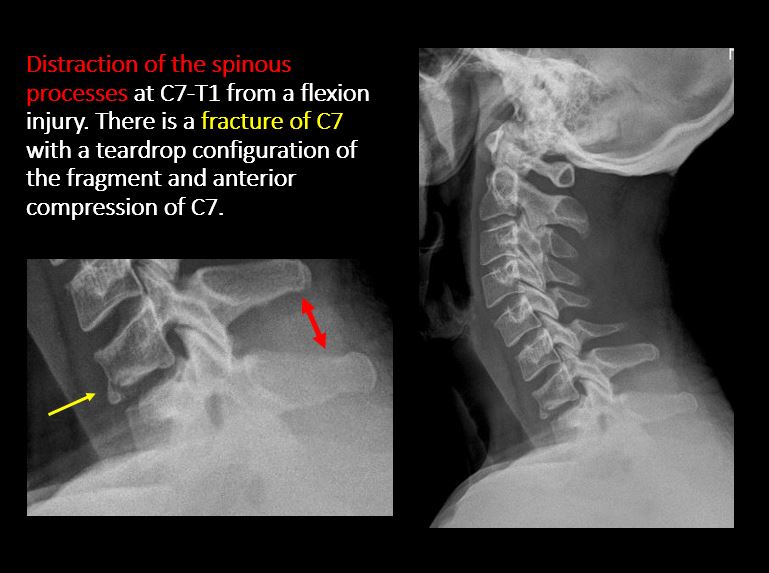

The visualized spinous processes are malaligned on the AP view or distracted on the lateral view. [Yes/No]

There is a fracture or distraction of a C3-T1 vertebral body, transverse or spinous process, or other posterior element. [Yes/No]

There is evidence of an end plate avulsion or other fracture. [Yes/No]

There is displacement of a fracture fragment into the soft tissues, spinal canal, or interlaminar clear zone of the spinal canal. [Yes/No]

There is anterior wedging or compression of a vertebral body or end plate. [Yes/No]